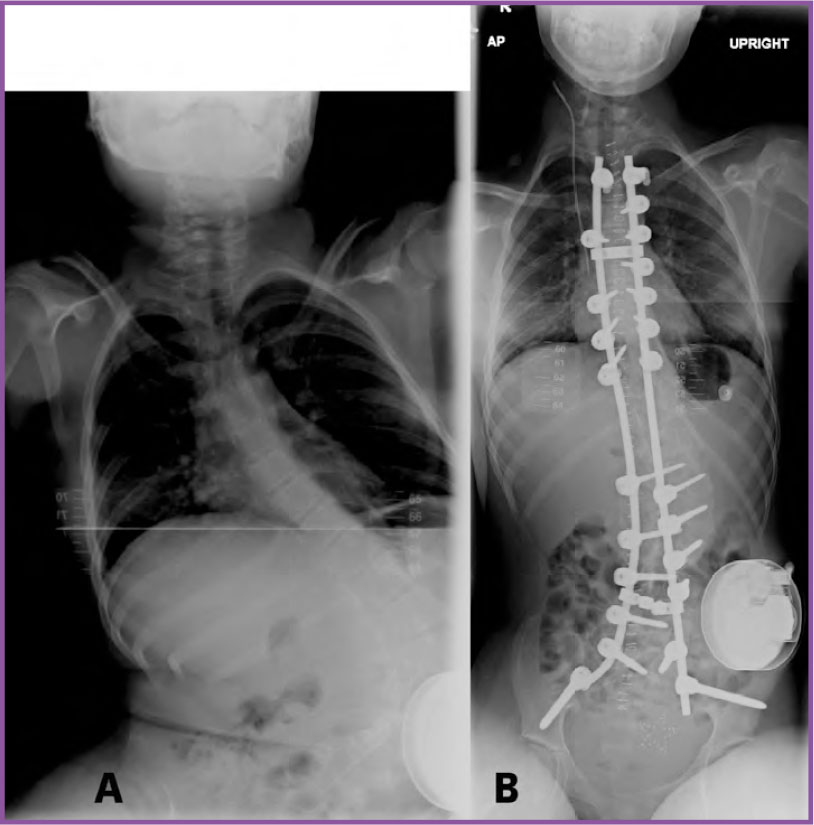

Friedreich S Ataxia Clinical Physio Membership Learn about friedreich’s ataxia (fa), a rare neurodegenerative disorder. explore symptoms, genetics, and current research initiatives. Friedreich's ataxia friedreich ataxia is the most common type hereditary ataxia and it is inherited in an autosomal recessive pattern. it is a slowly progressive ataxia with the age of onset in the first and second decades of life—usually below age 25. some individuals with friedreich ataxia may not develop symptoms until very late in life. Disease onset occurs typically in adolescence but can vary widely, ranging from early childhood to late adulthood. friedreich's ataxia is increasingly recognised as a multisystem disorder, affecting not only the nervous system, but also the heart and musculoskeletal system, and metabolism. Friedreich’s ataxia (fa) is a genetic, progressive neuromuscular disease. people with fa experience issues with balance and coordination of movement that lead to life altering loss of mobility. other common symptoms can include fatigue, serious heart conditions, scoliosis, and diabetes. Friedreich ataxia is an inherited disease that damages your nervous system. the damage affects your spinal cord and the nerves that control muscle movement in your arms and legs. Friedreich’s ataxia (af) is the most common autosomal recessive genetic cerebellar ataxia and affects about 1300 people in france, with symptoms usually occurring between the ages of 7 and 14.

Friedreich Ataxia Video Anatomy Definition Osmosis Disease onset occurs typically in adolescence but can vary widely, ranging from early childhood to late adulthood. friedreich's ataxia is increasingly recognised as a multisystem disorder, affecting not only the nervous system, but also the heart and musculoskeletal system, and metabolism. Friedreich’s ataxia (fa) is a genetic, progressive neuromuscular disease. people with fa experience issues with balance and coordination of movement that lead to life altering loss of mobility. other common symptoms can include fatigue, serious heart conditions, scoliosis, and diabetes. Friedreich ataxia is an inherited disease that damages your nervous system. the damage affects your spinal cord and the nerves that control muscle movement in your arms and legs. Friedreich’s ataxia (af) is the most common autosomal recessive genetic cerebellar ataxia and affects about 1300 people in france, with symptoms usually occurring between the ages of 7 and 14.